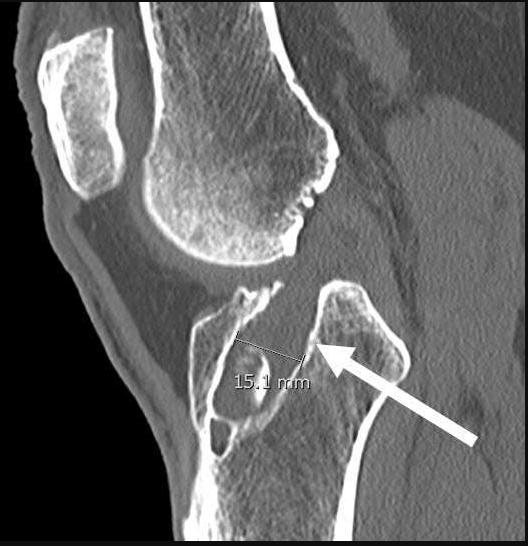

Revision ACL reconstruction often involves bone grafting to address specific tunnel issues. CT scans are crucial to evaluate the original tunnel's location and size. If tunnels are larger than 12 mm or mispositioned in a way that they intersect or overlap with each other, bone grafting becomes necessary to create a solid foundation for the reconstruction.